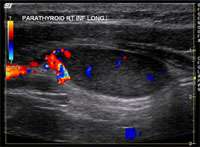

Most commonly, one of the four parathyroid glands have enlarged. However, it is possible to have two enlarged glands, or even mild growth of all 4 glands. Proper imaging tests help create a roadmap for a successful surgery. We routinely obtain multiple tests. Imaging of the parathyroid glands is challenging and sometimes the abnormal gland is not definitively seen by one or more imaging tests. That is because a normal parathyroid gland is the size of a grain of rice, and an abnormal gland may be the size of a green pea. Imaging is usually a combination of the following:

- Neck ultrasound, performed by the endocrine surgeon during the office visit